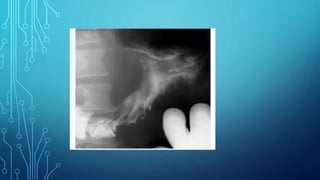

6. Fluoroscopy of the stomach: the main

symptoms are filling defect, the presence of

aperestaltic zones. Apithetic relief of the

mucous membrane, local thickening or

breakage of the folds of the mucous membrane.

Diagnostics 1. Complaints 2. Anamnesis 3.Palpation 4. Study of gastric contents 5. Blood test 6. Fluoroscopy of the stomach: the main symptoms are filling defect, the presence of aperestaltic zones. Apithetic relief of the mucous membrane, local thickening or breakage of the folds of the mucous membrane. 7. Gastroesophagoduodenoscopy 8. Biopsy